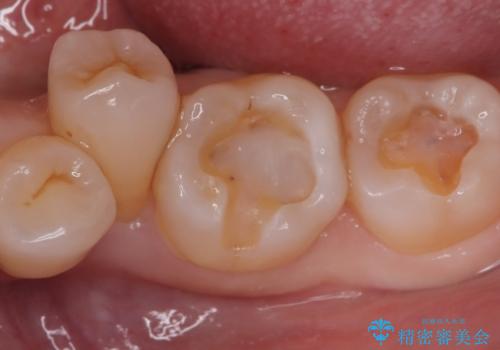

- 主訴:口を開けると所々入っている銀の詰め物が目立つので白い物にやり替えたい。

下顎大臼歯部に入っている保険適用のメタルインレーを、適合性と審美性の良いセラミックインレーでのやり替えとなりました。

メタルインレーを除去した際、古い裏層材やカリエスは除去し新たにCR裏層しています。

セラミックインレーセット時はラバーダム防湿を行っています。